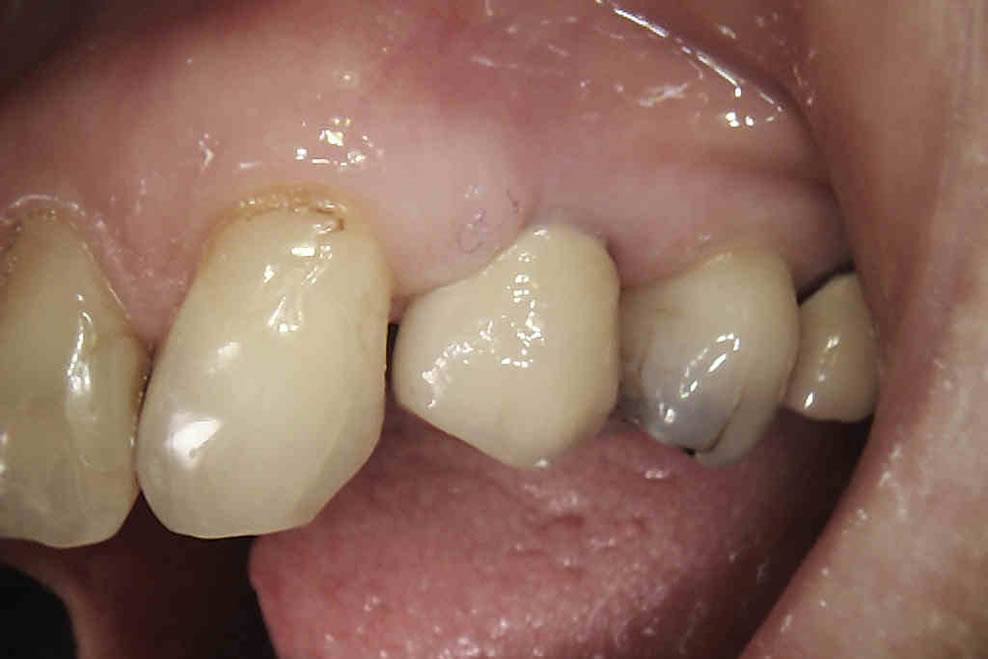

Dental implants are the best-known treatment to replace single or multiple missing teeth because they feel and behave just like natural teeth. After a while you won’t be able to tell the difference – even forgetting that they are there.

The procedure to place implants and replace a missing tooth or multiple teeth is straightforward as there is little need to treat surrounding teeth. Once a crown is placed over the implant it will appear indistinguishable from the natural teeth.

GIVING ANNETTE MORE CONFIDENCE WITH

DENTAL IMPLANTS